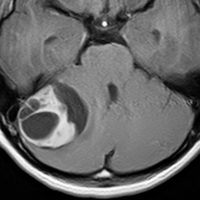

- 境界がはっきりした腫瘍です,くりんとしています

- ガドリニウム造影剤で白く映ります(増強される)

- でも,ガドリニウム造影剤が入らなくて白く映らないものもあります

- 周囲の小脳が腫れることが多いです(脳浮腫)